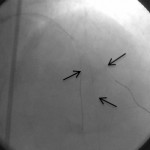

Çatallanma yapan üç damara 3 tel yerleştirilerek üç damara aynı anda müdahale ediliyor.